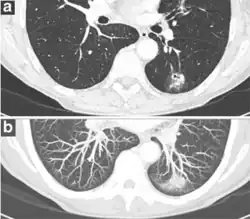

A lung nodule or pulmonary nodule is a relatively small focal density in the lung. A solitary pulmonary nodule (SPN) or coin lesion,[1] is a mass in the lung smaller than three centimeters in diameter. A pulmonary micronodule has a diameter of less than three millimetres.[2] There may also be multiple nodules.

One or more lung nodules can be an incidental finding found in up to 0.2% of chest X-rays[3] and around 1% of CT scans.[4]

The nodule most commonly represents a benign tumor such as a granuloma or hamartoma, but in around 20% of cases it represents a malignant cancer,[4] especially in older adults and smokers. Conversely, 10 to 20% of patients with lung cancer are diagnosed in this way.[4] If the patient has a history of smoking or the nodule is growing, the possibility of cancer may need to be excluded through further radiological studies and interventions, possibly including surgical resection. The prognosis depends on the underlying condition.